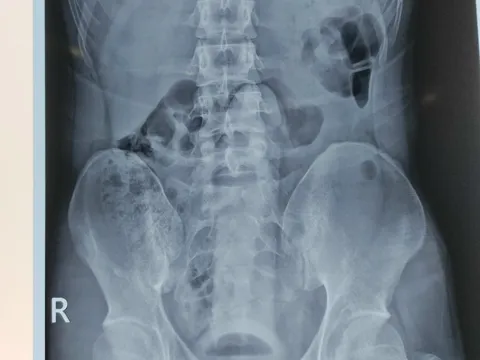

Nam thanh niên mắc kẹt đồ chơi tình dục trong... trực tràng

(NLĐO) - Dị vật dài 25cm mắc kẹt trong trực tràng nam thanh niên khiến vùng bụng dưới, hậu môn vô cùng đau đớn.